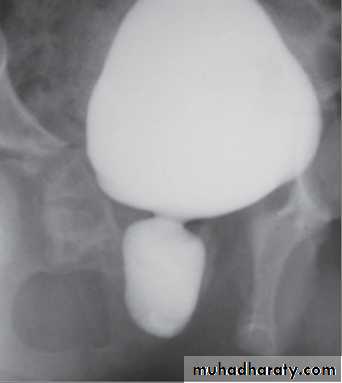

VCUG shows distended and elongated posterior urethra; partially filled anterior urethra; bladder neck hypertrophy; lucencies representing valve leaflets; thick-walled bladder (±diverticuli); incomplete bladder emptying; reflux (50%).

Prenatal US features These include bilateral hydroureteronephrosis, dilated bladder with elongated ectatic posterior urethra, thick-walled bladder, oligohydramnios, and renal dysplasia.Newborn and infants

These children have respiratory distress,palpable abdominal mass (hydronephrotic kidney or distended bladder), ascites, UTI, electrolyte abnormalities, and failure to thrive.